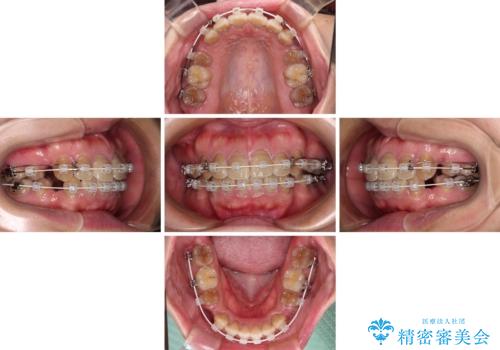

横顔の印象が大きく変わる ワイヤー装置での抜歯矯正

- 審美装置

- 2年6ヶ月

上下前歯が著しく前突している状態であったので、上下左右の第1小臼歯4本を抜歯し、ワイヤー装置にて矯正治療を行うこととしました。

4本の歯を抜歯したことで、飛び出していた口元が引っ込み、横顔が大きく改善されました。